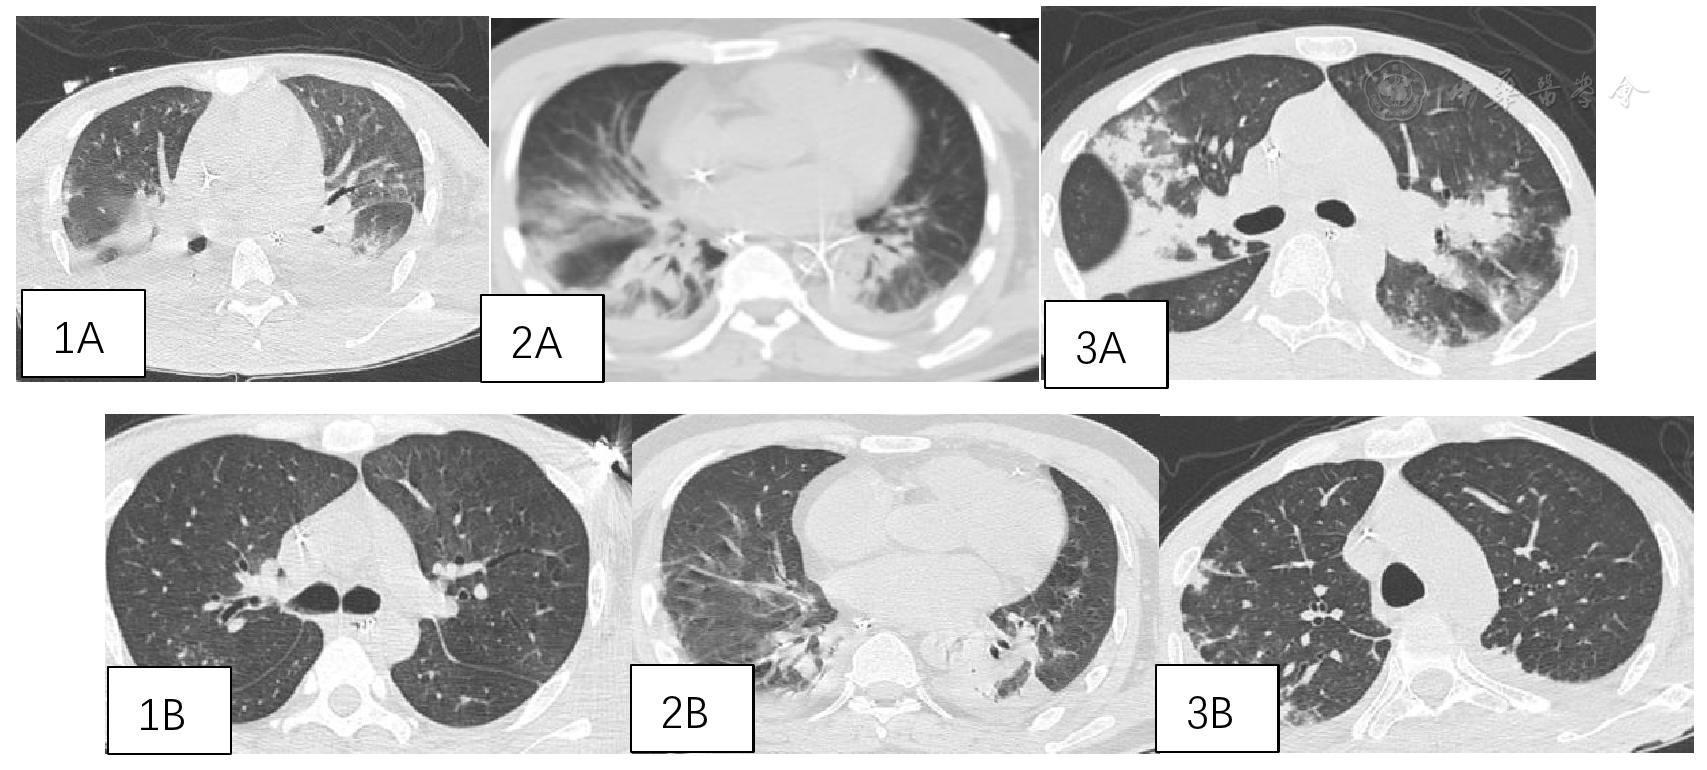

图2 3例患者治疗前后肺部影像学对比。图1A、2A、3A分别为病例1、2、3治疗前,图1B、2B、3B分别为病例1、2、3治疗2周后